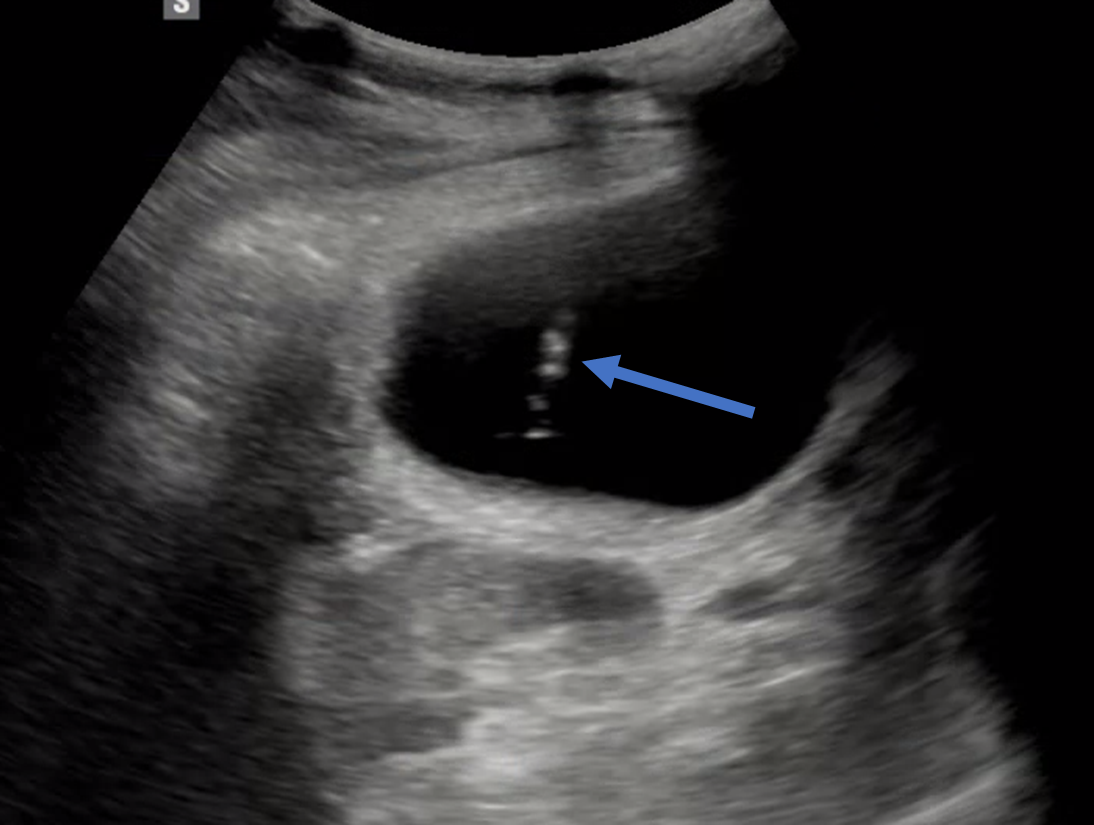

시술을 준비하며, 초음파로 먼저 담낭을 확인합니다.

그리고 정말 급성 담낭염이 맞는지 한 번 더 확인을 합니다.

확인 과정 중에 초음파 프로브로 배를 일부러 눌러봅니다.

일부러 염증이 있는 담낭을 압박해서 통증이 있는 지 확인하는 과정입니다.

이렇게, 정말 급성 담낭염이라는 것이 확인이 되면 들어갈 경로를 결정합니다.

바늘과 배액관이 진입할 경로에 다른 장애물이 있는 지, 안전한 시술이 가능할 지 확인하는 작업이죠.

그 다음 배액관이 들어갈 자리에 소독을 하고, 초음파로 늘어난 담낭을 보고 이를 바늘로 찌릅니다.

바늘로 담낭이 잘 찔려졌는지 엑스레이 장비로 실시간으로 확인한 뒤, 배액관을 삽입합니다.

왼손으로는 초음파를 보면서, 오른손으로는 바늘을 들고 담낭을 천자합니다.